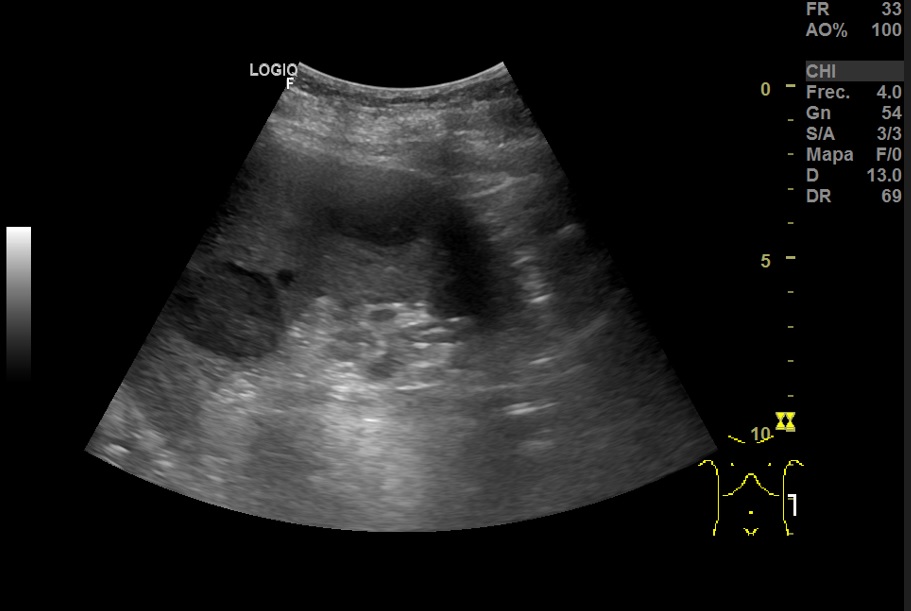

Hallazgos ecográficos

Hallazgos ecográfico: Esplenomegalia y varias lesiones focales hipoecogénicos de diferentes tamaños de bordes bien definidos en el bazo.